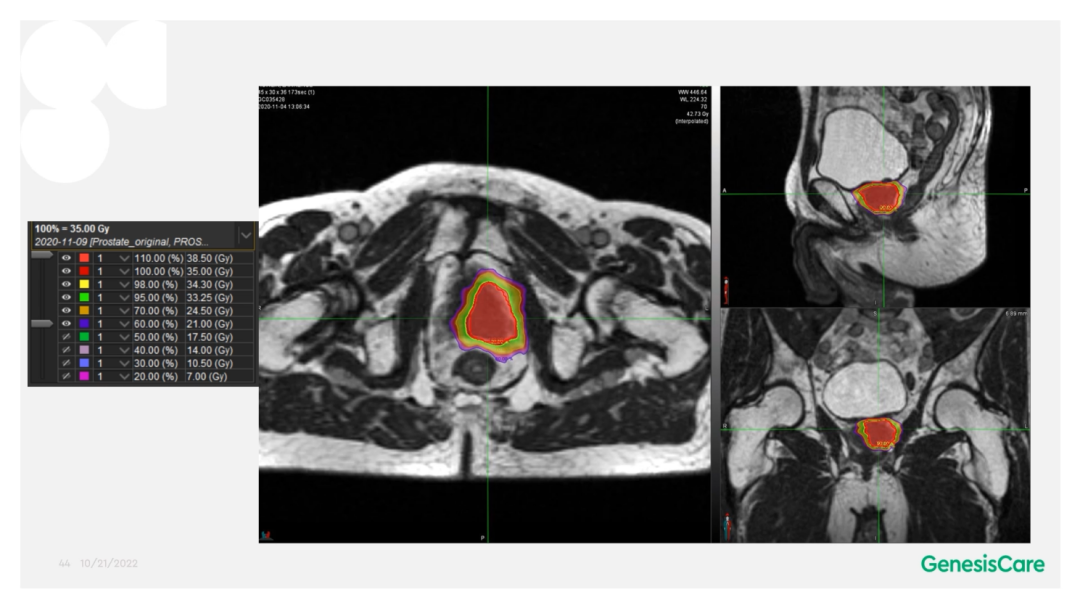

Dr. Camilleri介绍了一位72岁,在2006年接受了55Gy/20F放疗后复发的前列腺癌患者。当时它的PSA为28,局部晚期,期别为T3aN0M0。PET-CT显示前列腺左后部局部高代谢,活检也证实了这一点,并且活检结果表明肿瘤侵入左侧精囊腺底部。将其MRIdian MRI图像和PET-CT图像融合后,再根据活检结果确定靶区,见Figure 20-22,并制作放疗计划。放疗剂量为35Gy/5次,凝胶阻隔物很好地包含了直肠,见Figure 23,靶区和危及器官受量见Figure 24。患者于2020年12月接受治疗,他体质很好,在放疗期间和之后,坚持每周三次5公里跑步,始终未出现GU和GI毒性。他的PSA最低值为0.45,在2022年5月的随访数据中,睾丸激素水平回到了正常的33%。在2022年1月的放疗后PSMA PET的图像上,未见肿瘤高代谢见Figure 25。

Figure 23 放疗后复发的前列腺癌患者在MRIdian上的放疗计划

Figure 24 放疗后复发的前列腺癌患者放疗计划中靶区和危及器官的受量